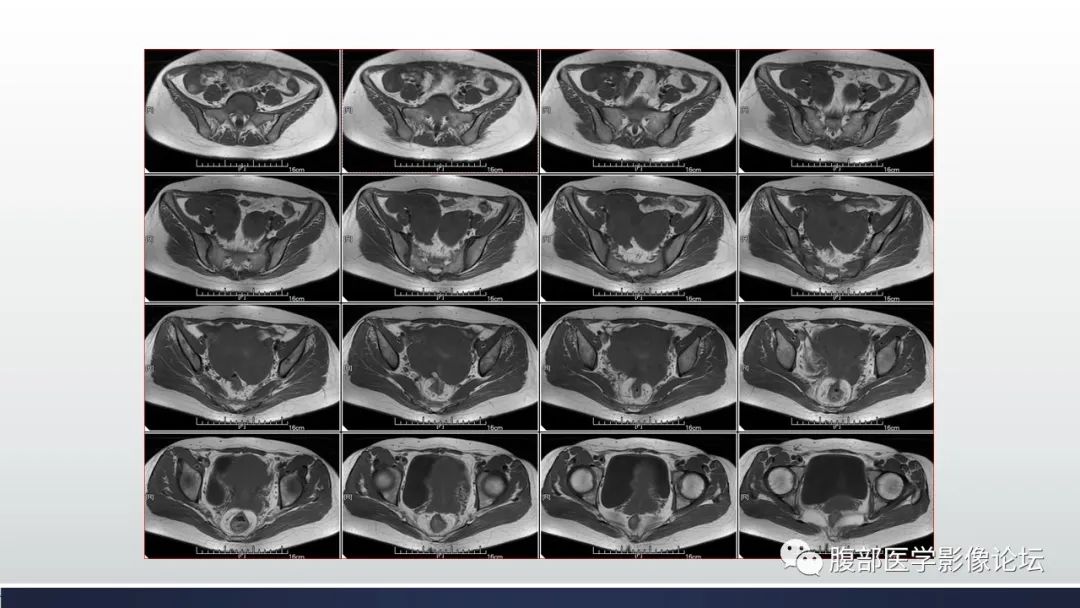

【病例】子宫内膜透明细胞癌1例MR-1